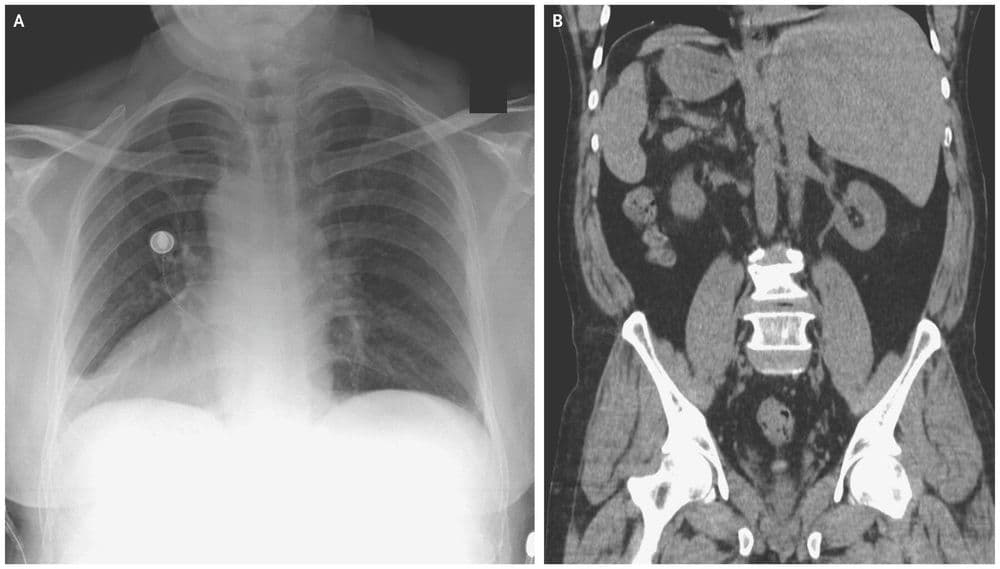

(हृदय उजव्या बाजूला)

जमालुद्दीन नावाचा हा माणूस नुकतंच पोटदुखीमुळे डॉक्टरांकडे आला होता. डॉक्टरांनी एक्स-रे काढल्यावर त्यांना धक्काच बसला. जमालुद्दीनच्या शरीरातील अवयव विरुद्ध बाजूला होते. त्याचं हृदय उजवीकडे आहे तर यकृत आणि पित्ताशय डाव्या बाजूला आहेत.

त्याच्या पोटात दुखण्याचं कारण होतं पित्ताशयात असलेले खडे, पण पित्ताशय डाव्या बाजूला असल्याने ऑपरेशन करणं अवघड झालं आहे. यासाठी आता नवीन तंत्रज्ञान वापरून त्याच्यावर उपचार केले जातील.

मंडळी, या प्रकाराला शास्त्रीय भाषेत Situs inversus म्हणतात. ही एक अवस्था असून यात माणसाच्या शरीरातील प्रमुख अवयव उलट्या दिशेत असतात. एकूण लोकसंख्येच्या अवघ्या ०.०१% एवढ्याच लोकांमध्ये ही अवस्था सापडते. बऱ्याचशा लोकांना आपल्या शरीरात असे उलटे अवयव आहेत हे माहितीच नसतं. त्याचा शरीरावर विपरीत परिणाम देखील होत नसतो.